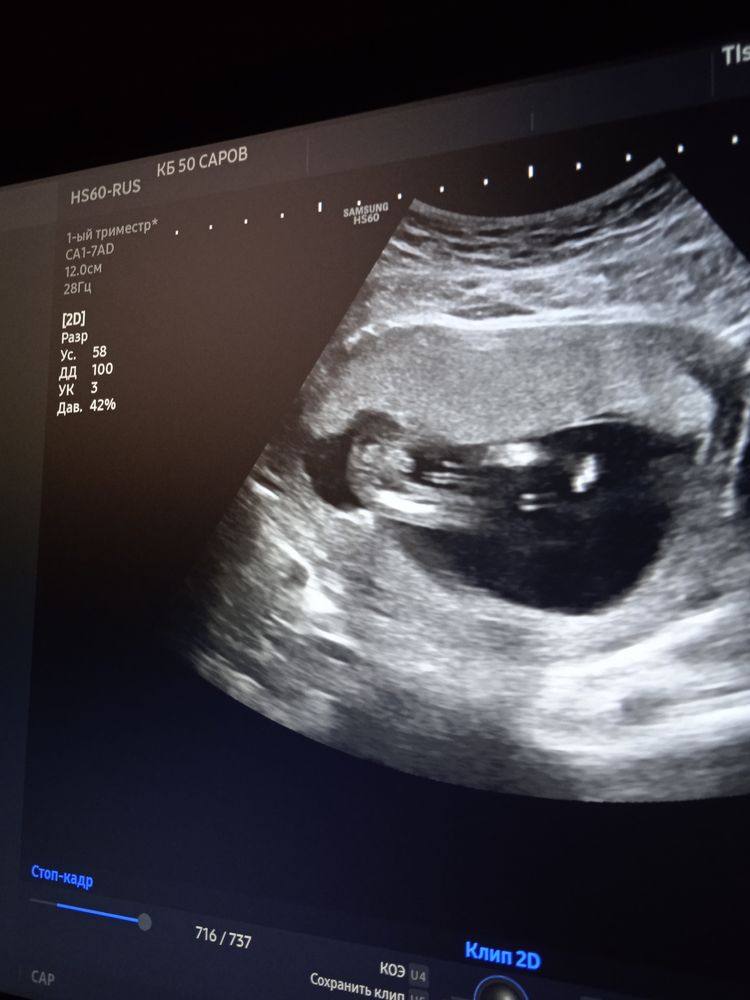

Мальчишка это))

ща покажу девочку на этом сроке))

Anya, спасибо🤗, сегодня на цервикометрии еле еле дался посмотреть, врач склонна к мальчику, но сказала всему своё время 🙌

В 11 недель по половому бугорку моя врач сразу сказала мальчик. В больнице на 16 неделе я видела именно такое изображение на экране узистка ещё раз подтвердила. Так и было.😎

Даша ЭдЛе, нам в 12.5 тоже сказали мальчик, а сегодня я че то тоже вроде вижу что торчит знатно, у девочек вроде всё более плоско,а чего то закрались сомнения🙈